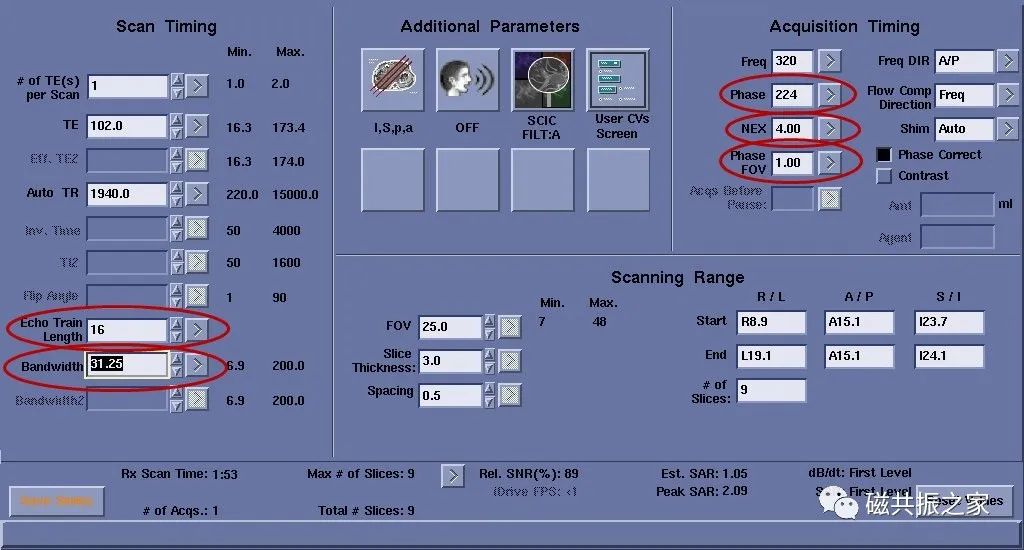

实际扫描中常更改的参数为回波链(ETL),带宽(BW),激励次数(NEX),相位编码数(Phase),相位FOV(Phase FOV),重复时间(TR)等。

回波链

回波链并不是越长越好,虽然一定长的回波链会减少扫描时间(并不是ETL越长,时间越短),但回波链的延长会引起TE值的延长(下图回波链16与20的区别),回波间隔的增加则引起图像模糊。同样长回波链会降低图像的信噪比。

同时回波链并不是越短图像就会越好,短的回波链会降低图像的T2对比(如长T2成像)。所以回波链应选取一个适当的值,这里要考虑的因素很多。通常T1WI:2-3个;PDWI:8-12个;T2WI:10-16个,但这不是绝对的,如果第一个回波时间值加上最后一个回波时间值的和除以2后的值与当前设置的TE值接近,那就是比较合适的。

激励次数

图1,NEX为4时,扫描时间为1:52,图2,NEX为2时,扫描时间为1:05。NEX相对于其它参数来讲它们间的影响是最小的,NEX值最直接的影响的是信噪比与扫描时间,如将NEX由4改为2后,相对信噪比由图1的100% 变了图2的71%。

相位编码

图1,Phase为224时,扫描时间为1:52,图2,Phase为192时,扫描时间为1:36。虽然相对信噪比由图1的100% 变了图2的108%,但会影响其图像分辨率。同时频率编码也会影响扫描时间。

相位 FOV

图1,Phase FOV为1时,扫描时间为2:41,图2,Phase FOV为0.7时,扫描时间为2:02。选择为1.0时,在相位编码方向上采集全部的信号;选择0.9时 ,为采集90%信号,周边作填零处理;选择0.8时,为采集80% 信号……这样做的好处就是节省了扫描时间,几乎不牺牲信噪比及分辨率。矩形像素与其类似。